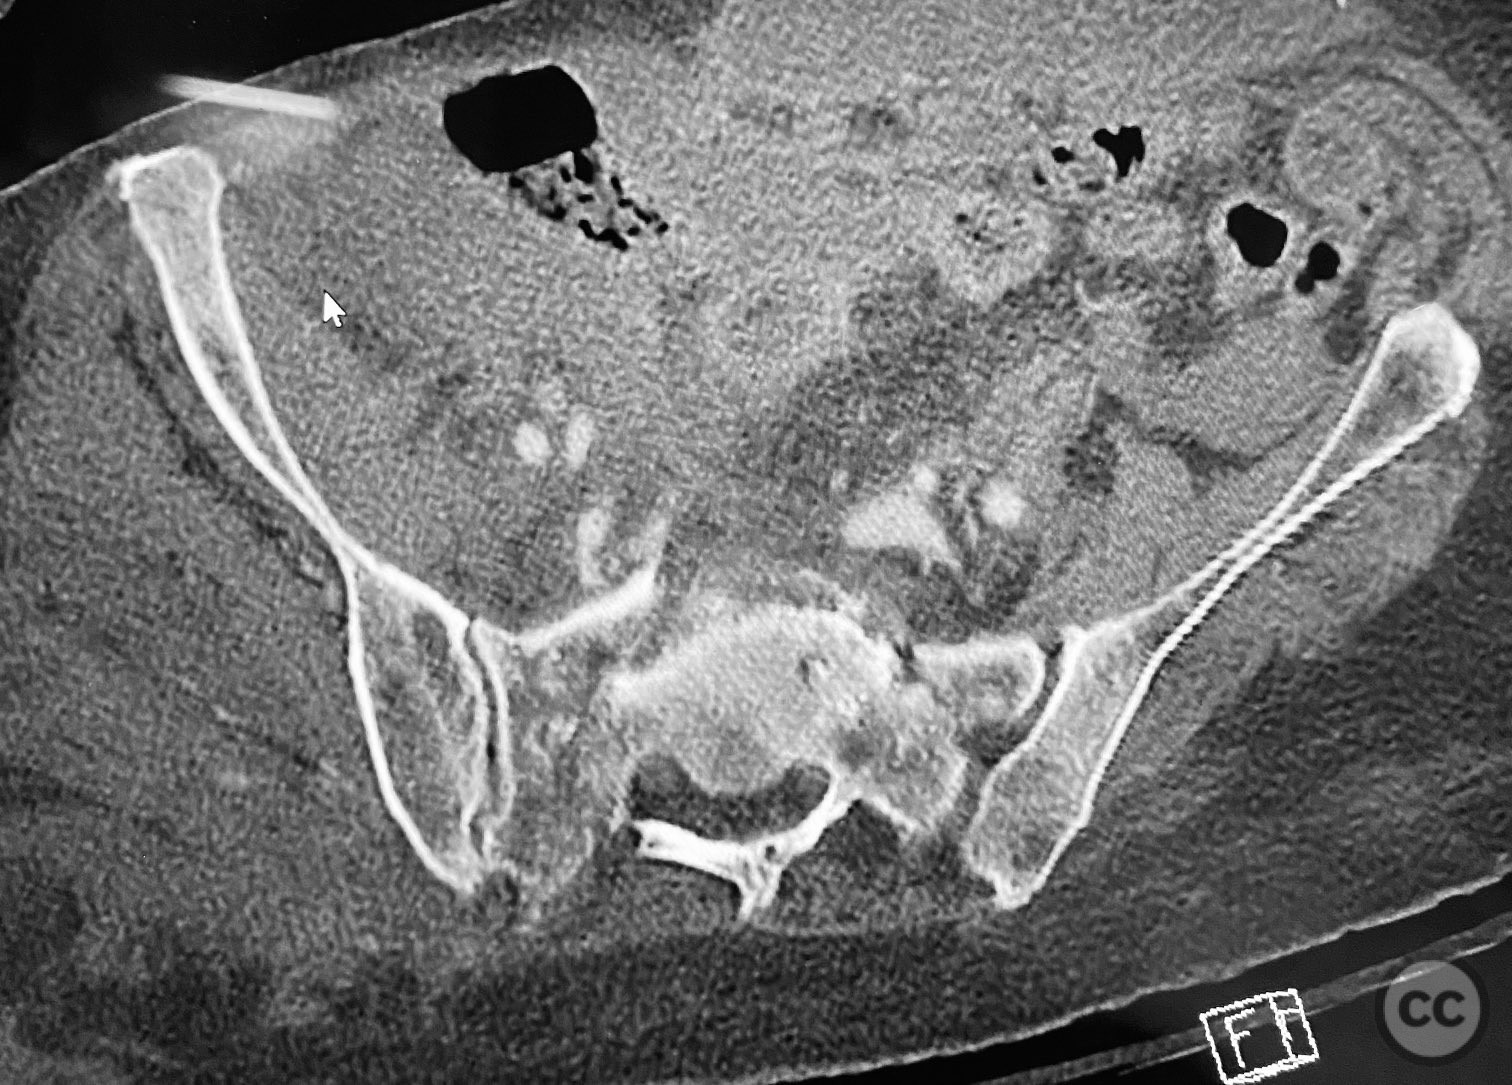

Clinical and radiological findings:  An elderly patient sustained multiple traumatic injuries, including complex unstable pelvic ring disruption (AO/OTA 61-C, likely C1 or C2 based on instability and comminution), comminuted proximal femoral fracture (AO/OTA 31-A3 or 31-B, depending on trochanteric or neck involvement), and significant abdominal trauma necessitating intra-abdominal packing. Initial clinical evaluation revealed hemodynamic instability and poor bone quality consistent with advanced age. Distal femoral traction was applied for provisional reduction. Radiological assessment was limited by osteopenia, fracture comminution, and the presence of abdominal packing materials.

Planning remarks:  The preoperative plan included early closed reduction maneuvers under fluoroscopic guidance, percutaneous stabilization of the pelvic ring with cannulated screws, and intramedullary nailing of the proximal femur. The anatomical approach for pelvic fixation was percutaneous iliosacral screw placement; for the femur, a standard antegrade intramedullary nailing technique was planned.

Anatomical surgical approach:  Percutaneous iliosacral screw fixation was performed through small lateral gluteal incisions, with blunt dissection to the outer table of the os ilium. Under fluoroscopic guidance, guidewires were advanced across the sacroiliac joint into the S1 body, followed by cannulated screw insertion. For the proximal femur, a longitudinal incision was made proximal to the greater trochanter, splitting the fascia lata and gluteus medius fibers to access the piriformis fossa. A guidewire was inserted into the medullary canal, followed by sequential reaming and insertion of an intramedullary nail.

Intraoperative imaging was challenging due to osteopenic bone, fracture comminution, and interference from abdominal packing. Accurate identification of safe osseous corridors for iliosacral screw placement required multiple fluoroscopic projections and careful attention to pelvic landmarks. Bone quality necessitated cautious screw advancement to avoid iatrogenic cortical breach. After pelvic fixation, intramedullary nailing of the proximal femur proceeded without complication. Abdominal packing was removed and laparotomy wound closed after skeletal stabilization. Early mechanical stabilization of both pelvic and femoral injuries was prioritized to optimize survivability in this multiply injured elderly patient.